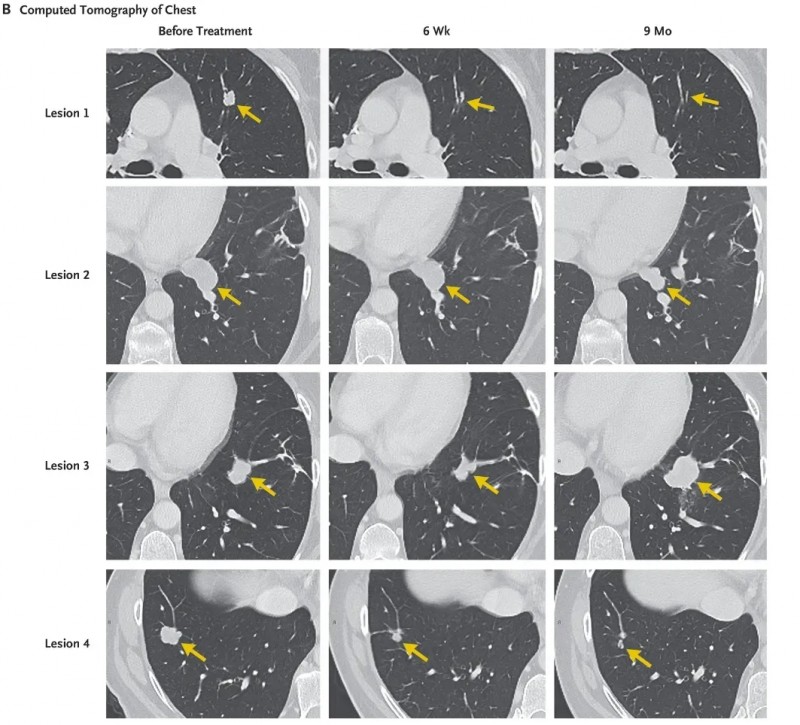

《费城问询报(The Philadelphia Inquirer)》报道了一则振奋人心的案例:一名转移性结肠癌患者接受肿瘤浸润淋巴细胞(TIL)细胞治疗后,肺部7个转移病灶全部实现消退,成功改写了“预后差”的命运!

这名患者47岁时出现疲倦、尿频、血便等症状,最终确诊为KRAS突变型结直肠癌。尽管先接受了初始手术治疗,但癌症仍持续进展——不仅扩散至膀胱、淋巴结,还进一步转移至肺部。后续尝试的手术、化疗、放疗等多种治疗方案,效果均不理想,病情陷入困境的她,最终入组了TIL细胞治疗临床试验。

治疗过程精准且严谨:医生先从患者肺部病灶切除组织中,提取并筛选出能特异性识别KRAS G12D突变的CD8+T细胞(这类细胞可精准锁定并杀伤肿瘤细胞);经体外扩增培养后,获得了1480亿个活性免疫细胞,通过静脉输注回输至患者体内;为进一步支持免疫细胞的生长与激活,后续还辅以白细胞介素-2(IL-2)治疗。

治疗效果远超预期:治疗40天后首次随访,CT检查显示,患者肺部7个转移病灶已全部消退。治疗后9个月复查,其中6个病灶仍维持完全消退或持续消退状态(详见下图),患者在此期间实现了9个月的部分缓解(依据实体瘤疗效评价标准)。仅剩余的病灶3未完全消退且出现进展,患者随后接受胸腔镜(VATS)手术切除该病灶及病灶2,术后正电子发射断层扫描(PET-CT)结果呈阴性,提示无肿瘤活性。

更为惊喜的是,截至目前,病灶切除术后已4个月,患者临床无任何疾病迹象。从确诊时担忧“活不过50岁”的焦虑,到如今顺利度过50岁生日的安心,她正满心期待未来陪伴家人的更多美好时光,TIL细胞治疗无疑为她点亮了生命的新希望!

▲图源“The Philadelphia Inquirer”,版权归原作者所有,如无意中侵犯了知识产权,请联系我们删除